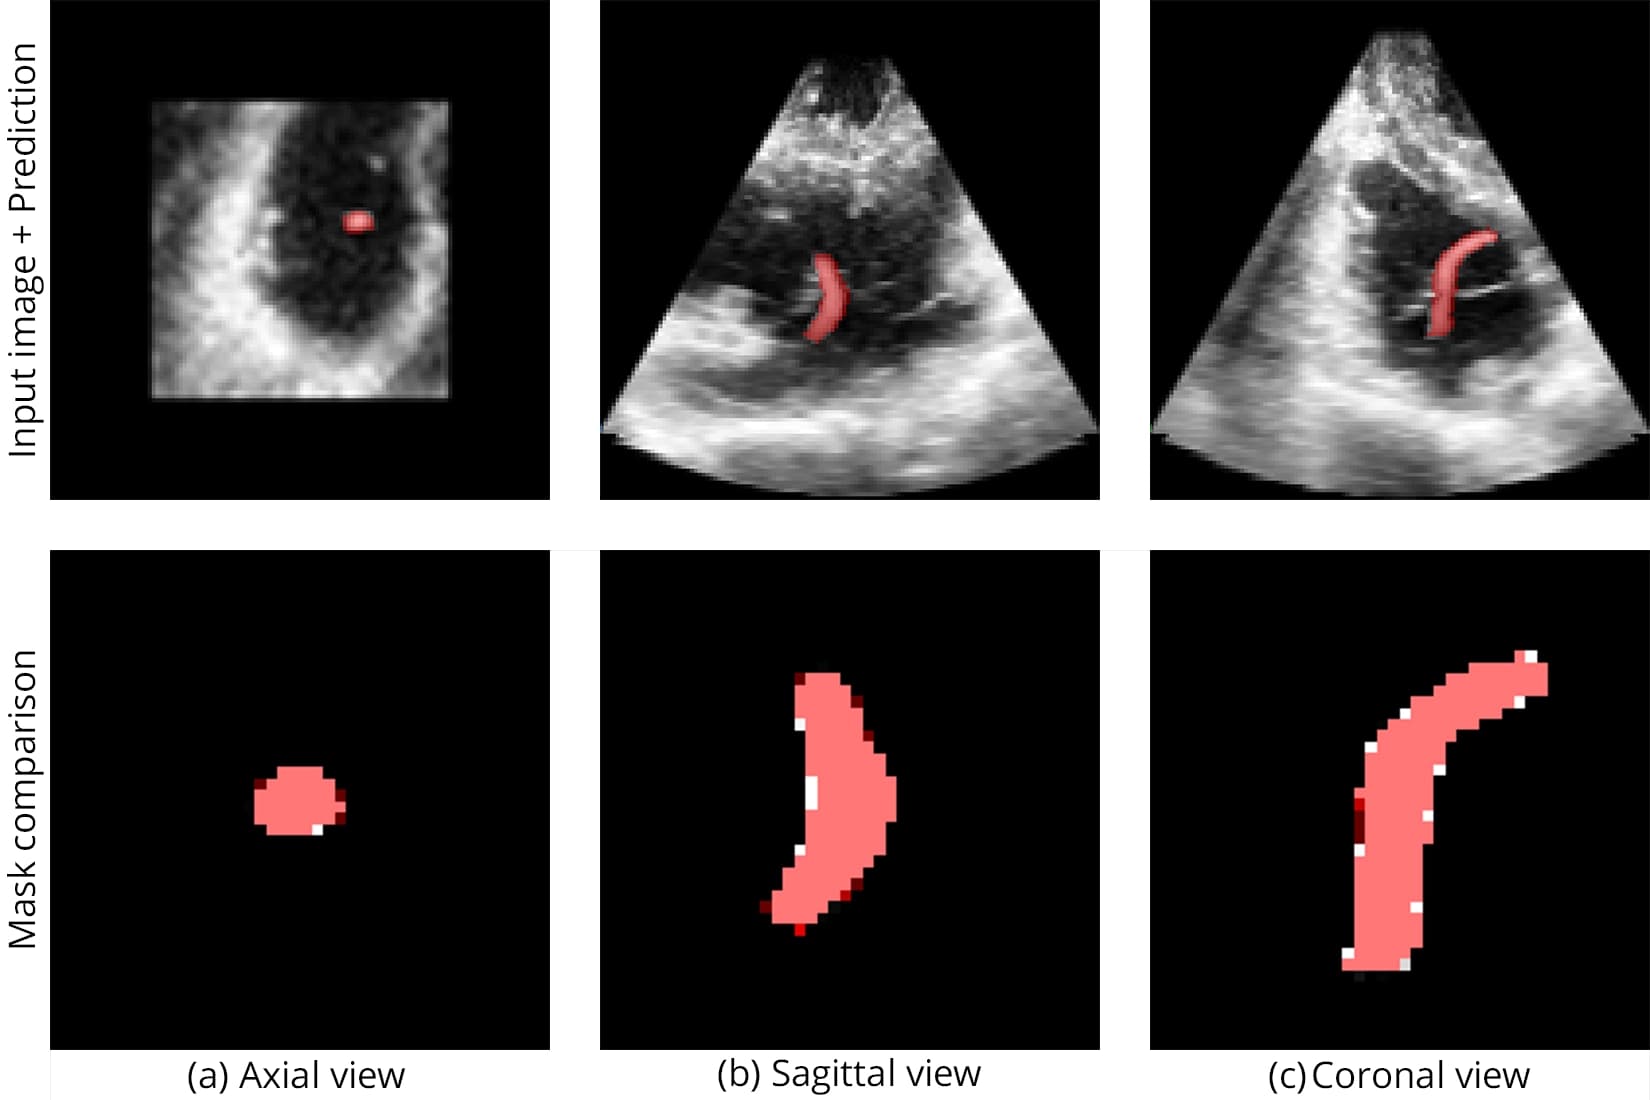

Segmentation accuracy on synthetic and real samples is shown in Figure 5 and Figure 6, and the comparison with other networks is presented in Figure 7.